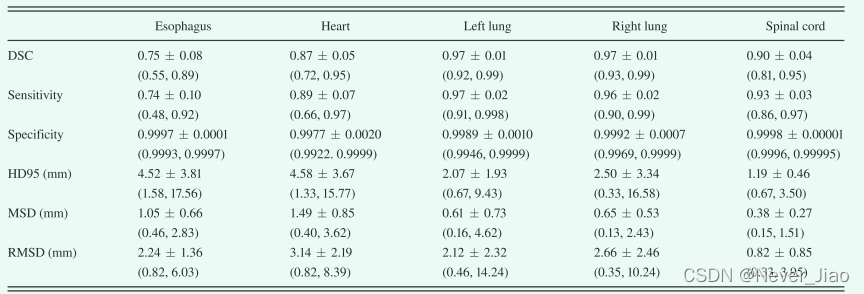

定量评估结果总结在图 5 和表 I 中。图 5 显示了对所有 35 名患者进行计算的六个评估指标——DSC、敏感性、特异性、HD95、MSD 和 RMSD,其平均值和标准差列于表中 I. 如图 5 和表 I 所示,所提出的方法在左肺、右肺和脊髓上实现了优异的分割精度,分别为 0.97、0.97 和 0.90 的平均 DSC,平均 HD95 为 2.07、2.50 和 1.19 毫米,所有平均 MSD 小于 1 毫米。由于图像对比度降低,心脏分割不如肺和脊髓分割简单。定量评估表明,所提出的方法与心脏描绘的基本事实非常吻合。平均DSC为0.87,平均HD95为4.58 mm,平均MSD为1.49 mm。在CT图像上,食管是五个器官中对比度最低的,因此最难描绘。提出的方法在食道分割上获得0.75±0.08 DSC、4.52±3.81 mm HD95和1.05±0.66 mm MSD。灵敏性评估真实的OAR体积与从该方法获得的体积重叠,而特异性量化真实体积之外的重叠部分。该方法的平均分割灵敏度为0.74–0.97,双侧肺最高,食道最低。这五种器官的特性几乎是一致的。五个器官的平均RMSD范围为0.8至3.1 mm。

Table.1 DSC、灵敏度、特异性、HD95、MSD 和 RMSD 的平均值和标准差。 括号中列出了最小值和最大值。